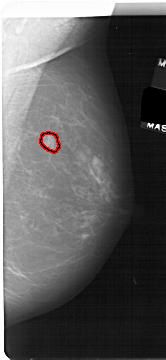

RIGHT_MLO LINES 5386 PIXELS_PER_LINE 2476 BITS_PER_PIXEL 12 RESOLUTION 43.5 OVERLAY

FILE: A_1694_1.RIGHT_MLO.OVERLAY

TOTAL_ABNORMALITIES 1

ABNORMALITY 1

LESION_TYPE MASS SHAPE LOBULATED MARGINS ILL_DEFINED

ASSESSMENT 4

SUBTLETY 2

PATHOLOGY MALIGNANT

TOTAL_OUTLINES 1

BOUNDARY